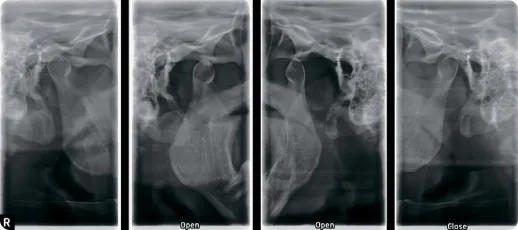

ВНЧС